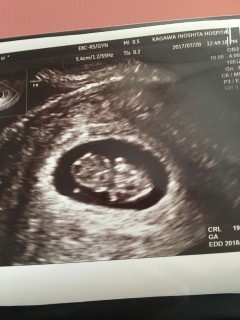

18.3mm!!卵黄嚢がホントに天使の輪みたいで天使すぎて可愛すぎて、もう親バカです w

元気に育ってねー´◡`

CRLは17mm弱

身体がゆらゆらした後、小さな手が動く様子を見ることができました(^^)

動画で撮影したのでずっと眺めてます♪

ママこんにちはって挨拶してくれたみたいで嬉しかったです!